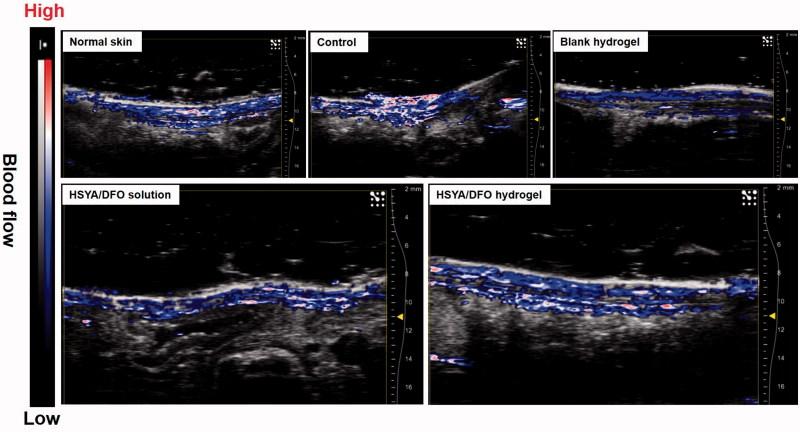

Nonhealing chronic wounds on foot induced by diabetes is a complicated pathologic process. They are mainly caused by impaired neovascularization, neuropathy, and excessive inflammation. A strategy, which can accelerate the vessel network formation as well as inhibit inflammatory response at the same time, makes it possible for effective diabetic ulcers treatment. Co-delivery of multiple drugs with complementary bioactivity offers a strategy to properly treat diabetic wound. We previously demonstrated that hydroxysafflor yellow A (HSYA) could accelerate diabetic wound healing through promoting angiogenesis and reducing inflammatory response. In order to further enhance blood vessel formation, a pro-angiogenic molecular called deferoxamine (DFO) was topically co-administrated with HSYA. The in vitro results showed that the combination of DFO and HSYA exerted synergistic effect on enhancing angiogenesis by upregulation of hypoxia inducible factor-1 alpha (HIF-1α) expression. The interpenetrating polymer networks hydrogels, characterized by good breathability and water absorption, were designed for co-loading of DFO and HSYA aiming to recruit angiogenesis relative cells and upgrade wound healing in vivo. Both DFO and HSYA in hydrogel have achieved sustained release. The in vivo studies indicated that HSYA/DFO hydrogel could accelerate diabetic wound healing. With a high expression of Hif-1α which is similar to that of normal tissue. The noninvasive US/PA imaging revealed that the wound could be recovered completely with abundant blood perfusion in dermis after given HSYA/DFO hydrogel for 28 days. In conclusion, combination of pro-angiogenic small molecule DFO and HSYA in hydrogel provides a promising strategy to productively promote diabetic wound healing as well as better the repair quality.